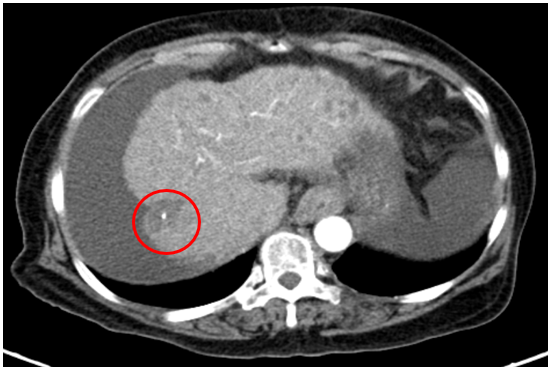

Chụp cắt lớp vi tính ổ bụng

Gan: Biến đổi hình thái, phì đại HPT I, bờ gan không đều. Nhu mô gan phải có khối giảm tỉ trọng kích thước 30x31mm, ranh giới không rõ, co kéo bao gan lân cận, tỷ trọng hỗn hợp, gồm phần tăng tỉ trọng của vật liệu nút mạch, phần tỷ trọng tổ chức vùng ngoại vi, sau tiêm ngấm thuốc mạnh thì động mạch, thải thuốc thì tĩnh mạch

Dịch quanh gan 22mm. Dịch tự do ổ bụng dày nhất 28mm

=>Hình ảnh u gan phải sau điều trị hiện còn phần ngấm thuốc sau tiêm (Vòng tròn đỏ), tăng nhẹ kích thước so với lần trước